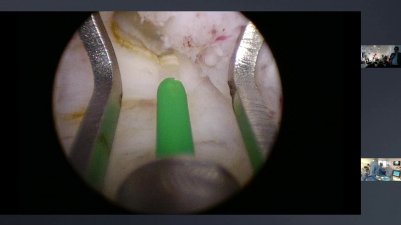

umpotolaryngologia

12:48 duration

0 likes